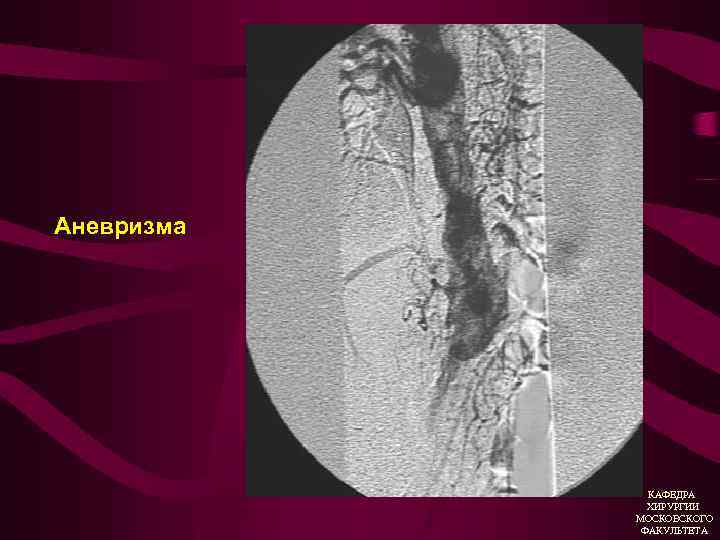

Дилятирующий атеросклероз Аневризмы 1. Истинная (расширение аорты или артерий в 2 раза и более без дефекта стенки 2. Ложная (паравазальная организованная пульсирующая гематома, вследствие дефекта в стенке аорты или артерии). КАФЕДРА ХИРУРГИИ МОСКОВСКОГО ФАКУЛЬТЕТА

Атеросклеротическая аневризма брюшной аорты • Боль (симптомная аневризма) • Атеросклеротический анамнез • Пульсирующее образование в брюшной полости, аускультативно систолический шум • УЗИ (дуплексное ангиосканирование) • Ангиография КАФЕДРА ХИРУРГИИ МОСКОВСКОГО ФАКУЛЬТЕТА

Аневризма брюшного отдела аорты КАФЕДРА ХИРУРГИИ МОСКОВСКОГО ФАКУЛЬТЕТА

Аневризма грудного отдела аорты КАФЕДРА ХИРУРГИИ МОСКОВСКОГО ФАКУЛЬТЕТА

Аневризма КАФЕДРА ХИРУРГИИ МОСКОВСКОГО ФАКУЛЬТЕТА